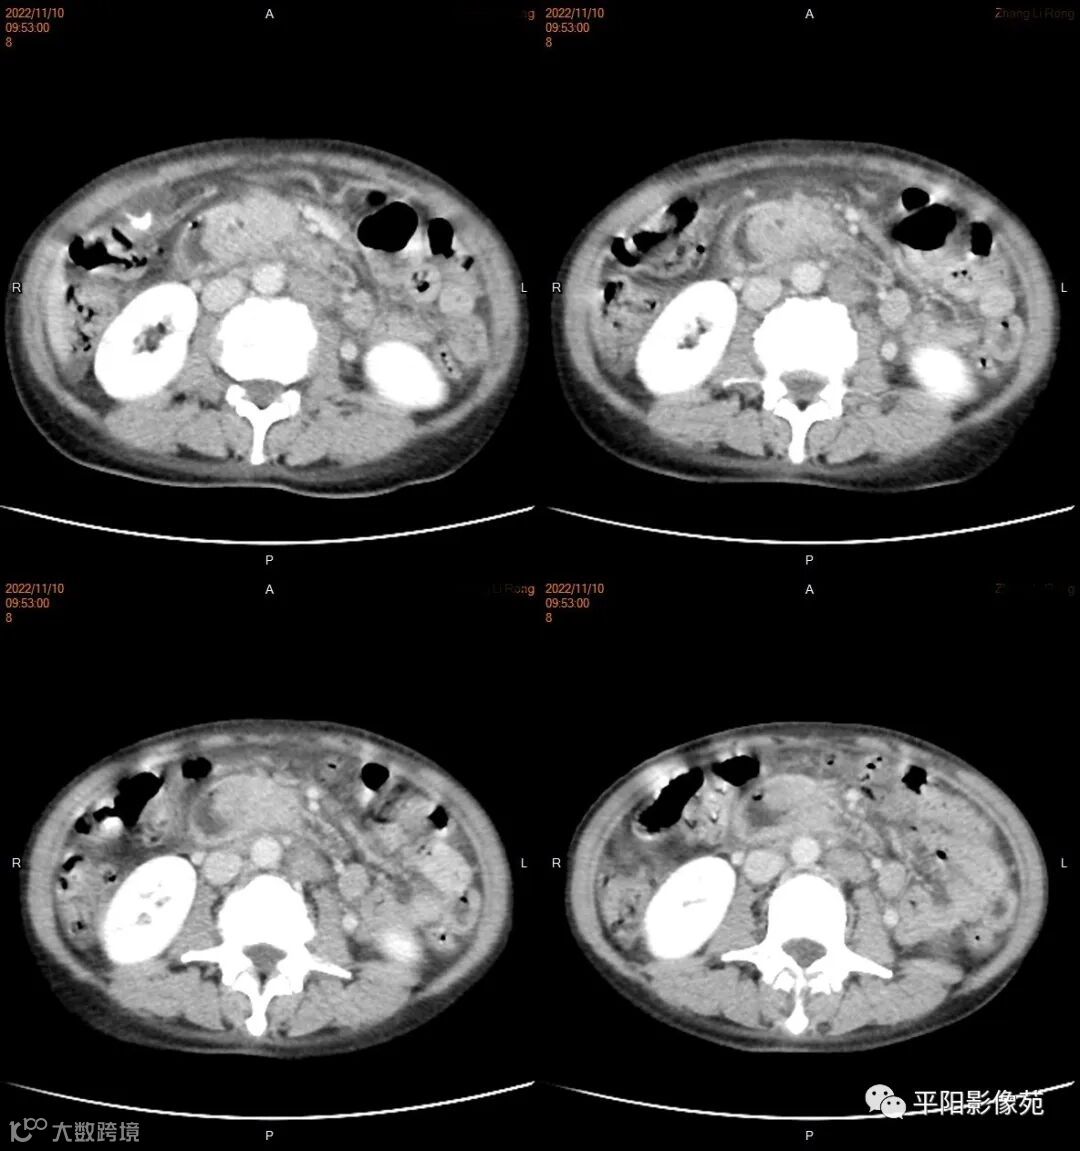

影像学检查

CT

肿瘤病理基础以肉眼形态分型可分为息肉型、溃疡型、缩窄型、弥漫狭窄型。

影像表现: